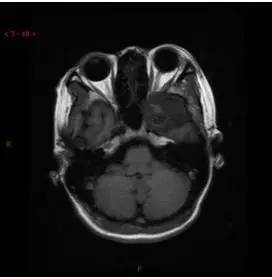

T1WI轴位

解析:本病例为中颅窝至颞下窝沟通性病变,对周围骨质主要呈膨胀压迫性改变,伴囊变、出血。

病理:(中颅底内外沟通肿瘤) 神经鞘瘤,伴出血,局灶细胞较丰富。免疫组化结果显示:EMA(-), P53(-), S100(3 ), NF(-), PR(-), desmin(-), Ki-67( ,5-10%)

神经鞘瘤